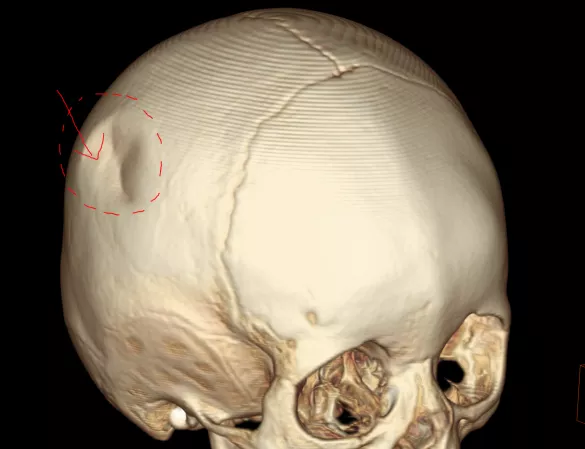

下面這一位1歲的孩子坐在沙發上玩,孩子媽媽只是轉身去拿個東西,就在這一瞬間,孩子從沙發上摔了下來,頭先著地,導致顱骨凹陷性骨折。

這種骨折如果不及時處理,骨折端可能會向大腦方向生長,從而刺破大腦,造成二次傷害。